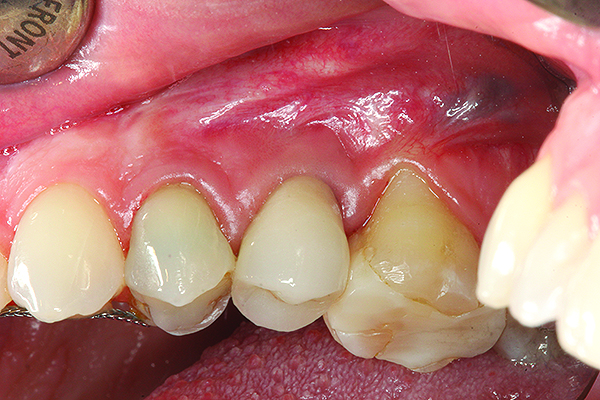

A implant restoration with a buccal dehiscence of bone and soft tissue caused by poor implant positioning, lack of keratinized tissue prior to implant placement, and soft tissue recession post implant restoration.

Figure 8

The same implant in Fig 8, 7 years following treatment, which included two autogenous connective tissue grafts and a bone augmentation surgery with a combined allograft and xenograft mixed with two biologics.

Figure 9